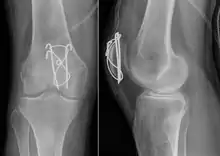

Surgery

Most patella fractures are transverse or comminuted, hence the quadriceps mechanism is disrupted and they are treated by a combination of wires in a tension band construct. This unites the fractured bones, reconstructing the straightening mechanism of the leg.[5][6]

If the patella is broken in several places, that is comminuted, then traditionally a patellectomy (removal of the whole patella) is performed in order to reconstruct the extensor mechanism and prevent the onset of an extension lag at the knee joint, resulting in instability.[5][8][9] Some surgeons however would rather opt for internal fixation.[8] A partial patellectomy is removal of only a portion of the patella, and may be carried out if at least 60% of the patella can be maintained.[6][8]